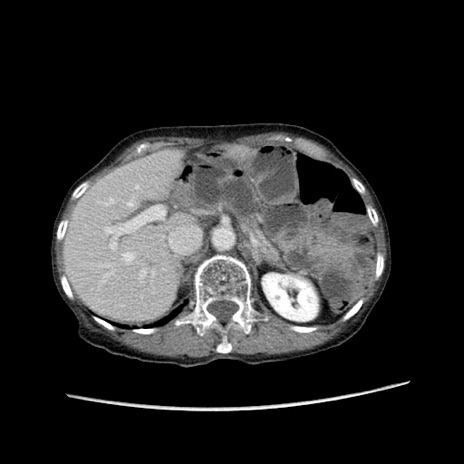

症例25(横断像)

【症例】80歳代女性

【主訴】胸のつかえ感

【現病歴】約9時間前に食後から胸のつかえた感じあり、嘔吐あり、来院。

【既往歴】胃癌(全摘)、胆摘、虫垂炎

【身体所見】心窩部に圧痛あり、反跳痛なし。

【データ】WBC 5700、CRP 0.05